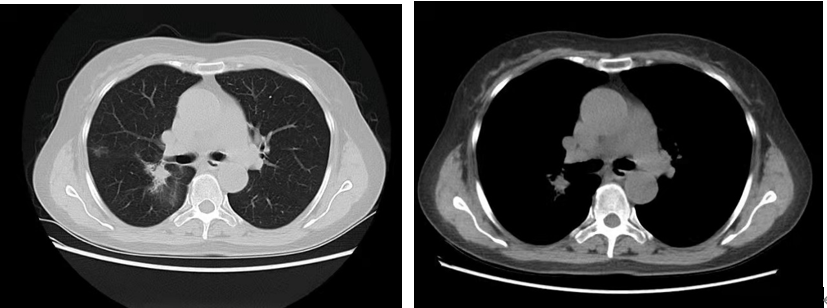

治疗前基线:右肺上叶多发结节,大者(2.3*2.0*2.1cm)考虑恶性。

治疗2月后:(SD)右肺上叶多发结节,大者(2.0*1.5*1.8cm)恶性可能性大。

治疗8月后:(PR)右肺上叶多发结节,大者(1.2*1.1cm)较前明显缩小。

治疗13个月后(2021-8):(PR)